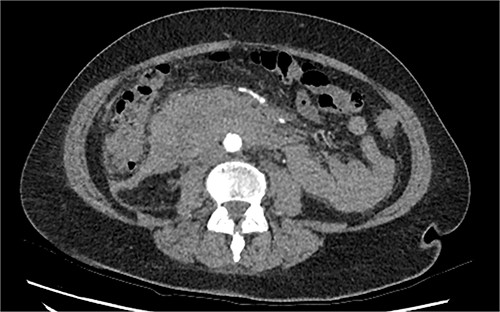

The radiologist suggested a computer tomography (CT) scan to further explore the potential causes for this fluid. The CT abdomen and pelvis revealed extensive oedema and induration surrounding the duodenum with a complex hyperdense fluid, extending from this site to the paracolic gutters and into the pelvis. While these findings are suspicious of a paraduodenal hemorrhage from a ruptured duodenal ulcer and hemoperitoneum, they were not typical for perforated duodenal ulcer or erosion into the blood vessels. Differentials were an infiltrating mass either fibrotic or of a lymphoproliferative origin. However, this could not explain the complex fluid in the abdomen (Figs 1 and 2).

CT abdomen, axial view. Hyperdense fluid centered around the duodenum and tracking into the paracolic gutters. Appearance concerning for paraduodenal hemorrhage, infiltrating mass was considered less likely.